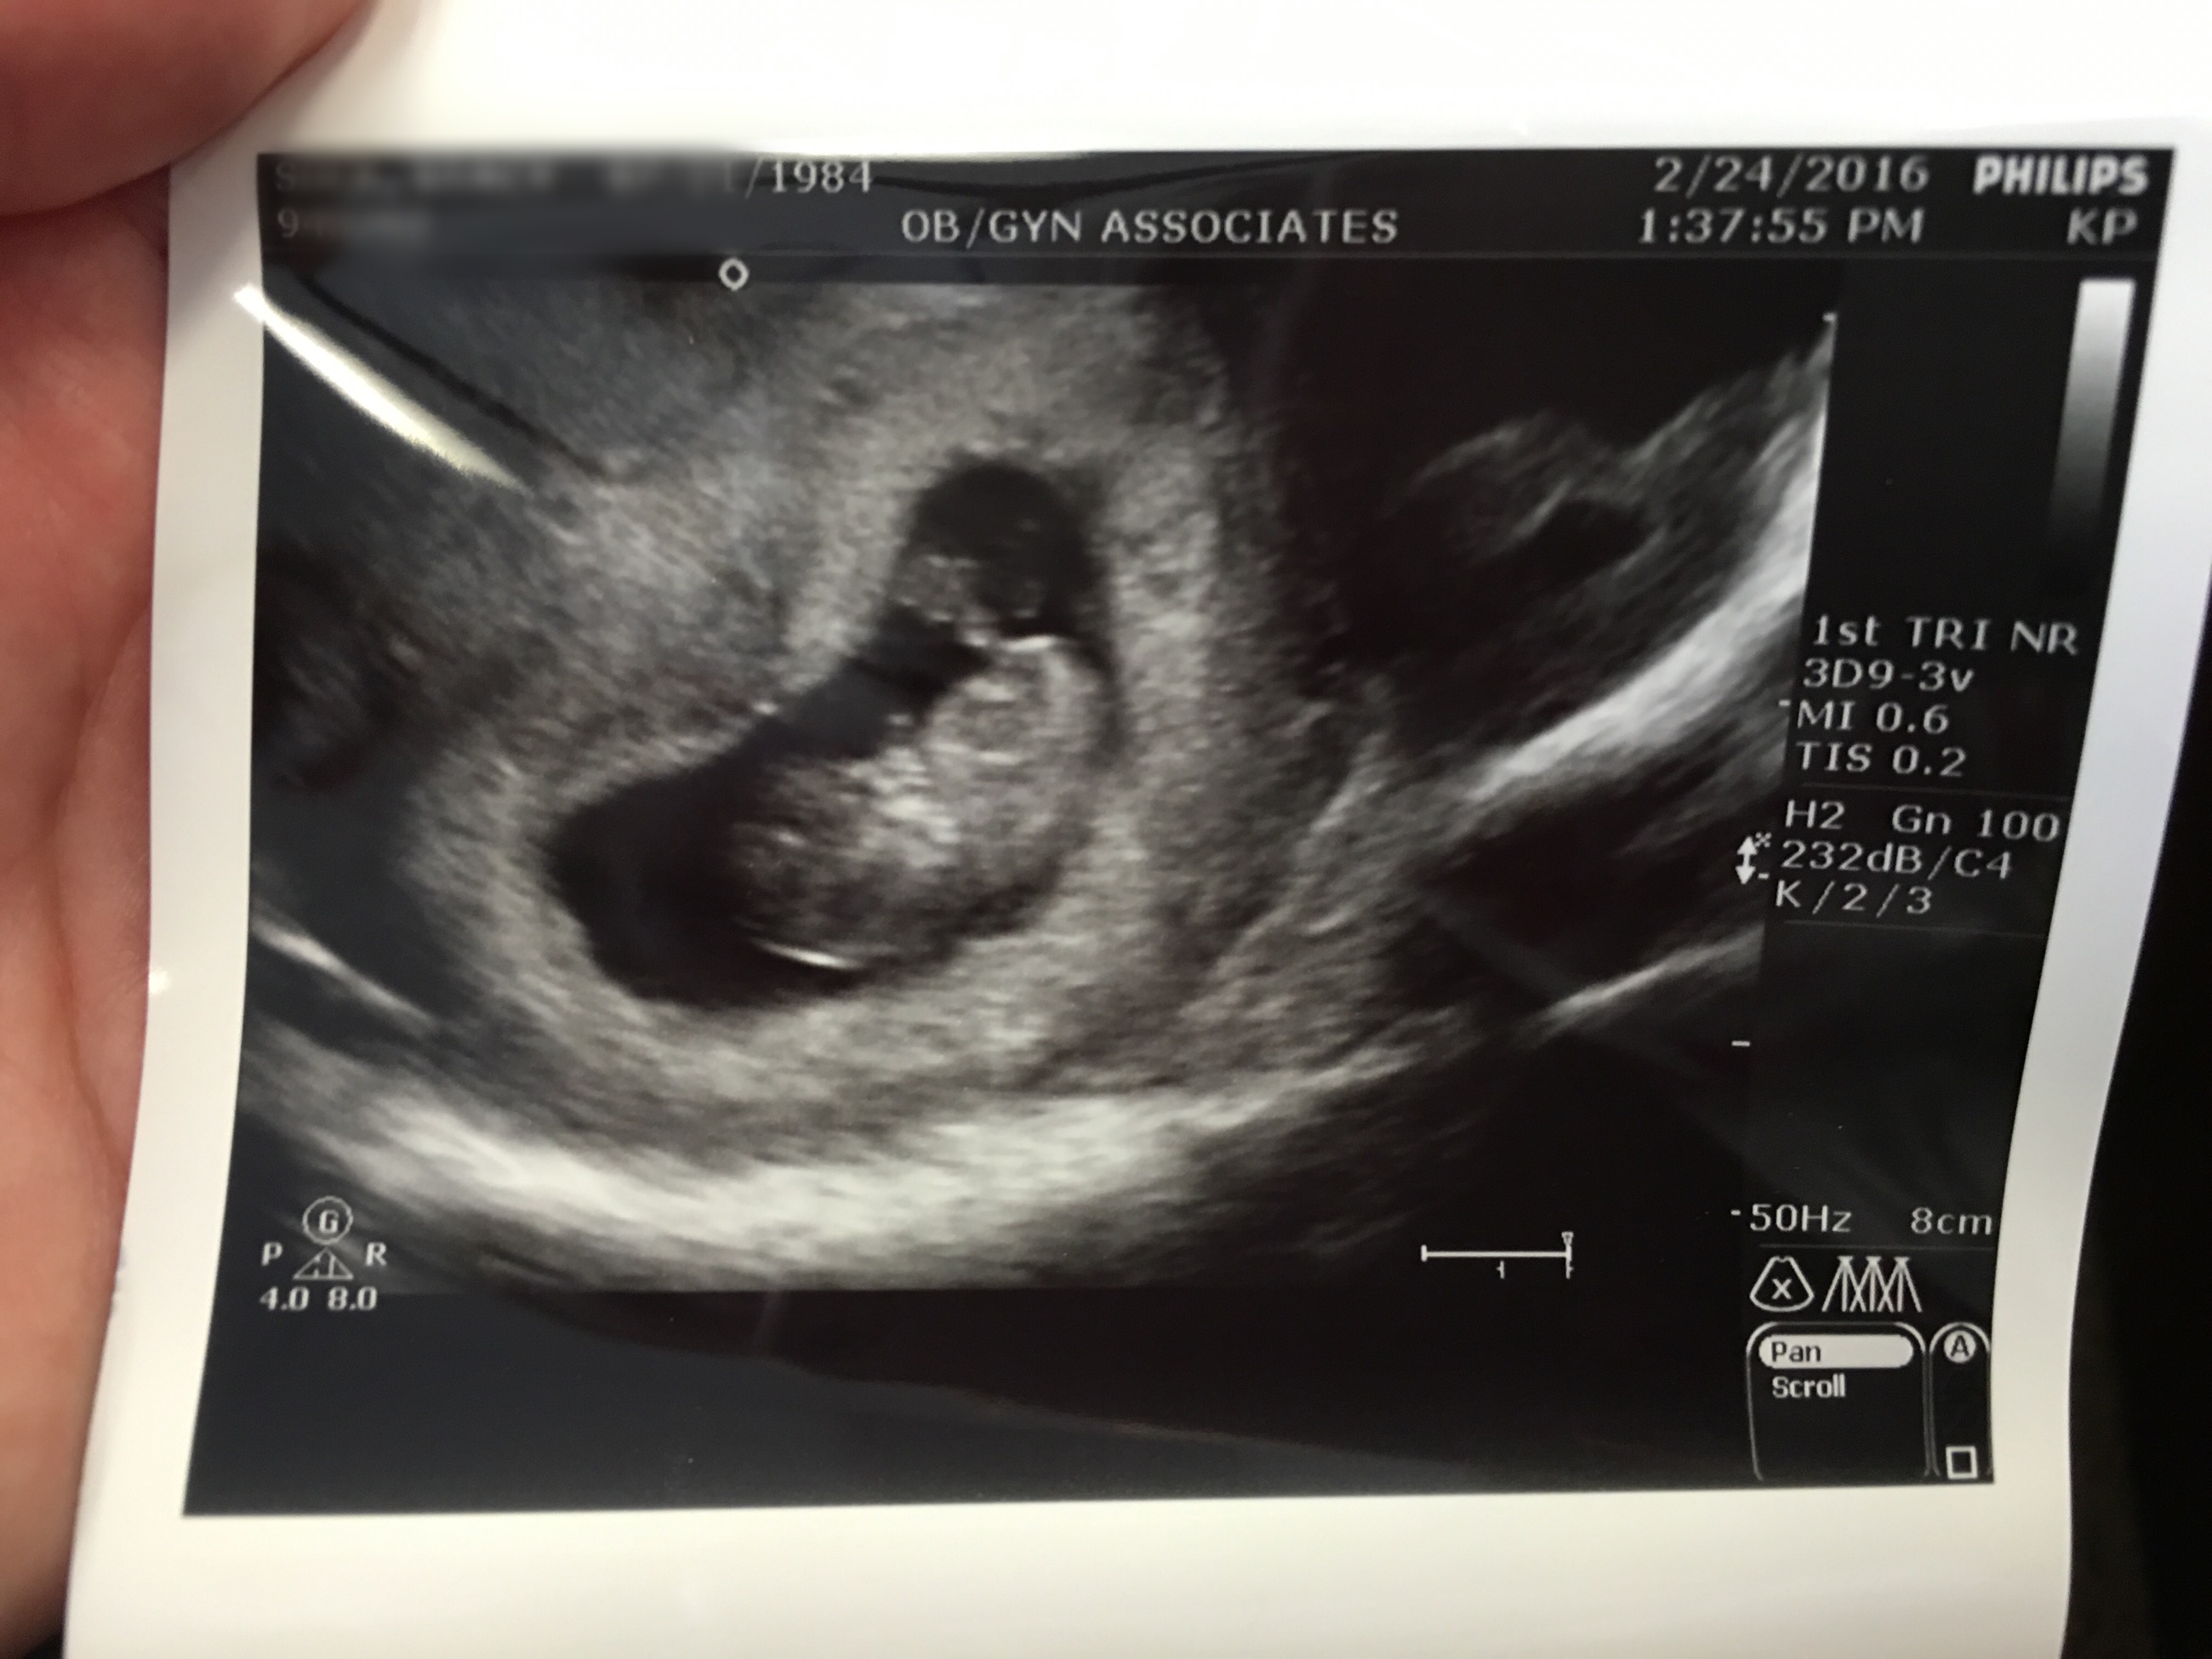

Best moment the week: Knowing that everything was okay with the baby after we had a small scare of bleeding (more than just spotting) and cramping that was making me unable to move off the couch all day. We went to the OB as soon as they could get us in (not soon enough) and did an ultrasound and pelvic exam and found no source of bleeding and my cervix was closed and thick (per the doc). We did get to see the baby again and the heartbeat and I immediately felt better. I was thanking the good Lord. HR was 178 and measuring exactly 9 weeks. So far so good. After that day of cramping I rested well and the next day I felt back to normal. Luckily we have Shantel in our lives to watch Josie and she was available at the drop of a dime to watch her while we went to the OB. I can’t thank her enough for all she does and continues to do. She’s simply the best. We are so grateful.

What a difference a week makes! I saw arm buds, leg buds and even fingers (in another US picture). The head is down below. HR 178 and measuring 9 weeks. The cyst on my left ovary is 3 cm and has not grown (or shrunk), they do not think that is the source of the bleeding. I am thinking that it could be the remaining blood surrounding my uterus from a previous cyst that ruptured when I miscarried in December.